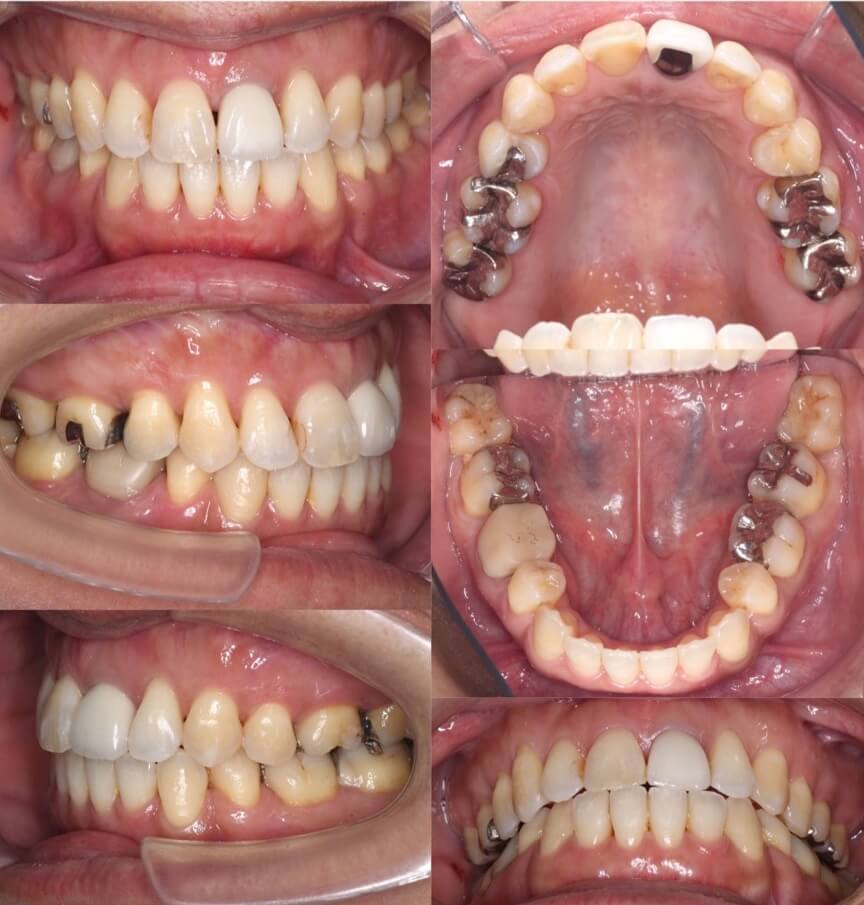

46歳女性・唇側矯正装置・抜歯

<症例概要>

主訴:前歯と口元の突出

年齢・性別:43歳女性

住まい:千葉県佐倉市

症状:叢生・上下顎前歯唇側傾斜

治療方針:上左右5番・下左右4番(計4本)

治療装置:唇側矯正装置

固定装置:ナンスホールディングアーチ

治療期間:3年

リテーナー:下フィックス+上下クリアタイプ

治療費用:968,000(税込)

代表的副作用:痛み・治療後の後戻り・歯根吸収・歯髄壊死・歯肉退縮

▶︎その他の副作用

前歯の突出のため口が閉じづらいことを気にされていて矯正治療を希望された患者さんです。年齢的に抜歯を行うか迷ったのですが、患者さんの主訴を優先して抜歯矯正により前歯を後方移動させました。抜歯部位については、上の歯並びは治療歯である第二小臼歯(5番)を選択しています。その分、治療期間は3年を超えてしまったのですが、理想的な横顔になりました。